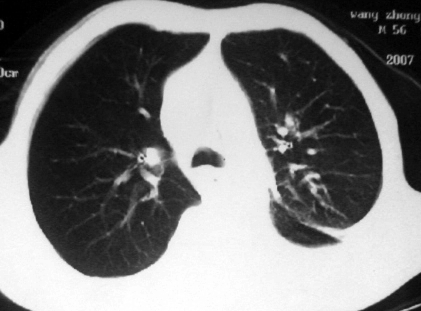

男,54岁,咳嗽,气喘半年,胸痛一月.

血性胸水

左侧胸腔积液 斜裂积液 心包积液 左肺不张 考虑左肺ca并胸膜心包转移。

支持左肺下叶中心型肺癌(累及舌叶)伴阻塞性肺炎、膨胀不全、胸腔积液、心包少量积液。

考虑左肺下叶中央型肺癌伴阻塞性肺炎及肺不张,纵隔受累可能,胸膜转移。